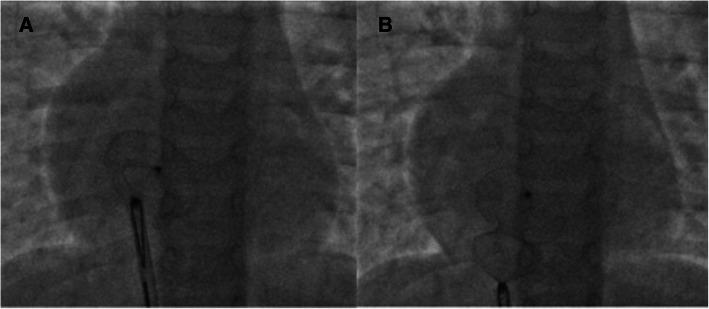

A 5-year-old asymptomatic child was found to have a murmur on a routine check-up. Evaluation revealed a haemodynamically significant, 18-mm ostium secundum ASD with normal pulmonary pressures and suitable margins for device closure. A 20-mm ASD closure device was traversed via an 8-Fr delivery system. While manipulating the left atrial (LA) disc from the right upper pulmonary vein (RUPV) approach, the device got spontaneously released. The right atrial (RA) disc was caught across the ASD, into the left atrium. This was confirmed by intraoperative transthoracic echocardiography and fluoroscopy. The haemodynamics and rhythm were stable. A 20-mm gooseneck snare was immediately passed through the delivery sheath and an attempt was made to catch the screw. With difficulty, the RA screw was caught with the snare and multiple attempts to retrieve the device into the sheath were unsuccessful. However, while negotiating, we were able to secure a favourable position of the device across the atrial septal defect, and after fluoroscopic and echocardiographic confirmation, the device was released. The child remained stable thereafter and was discharged 2 days later.

一名5岁无症状儿童在常规体检时被发现有杂音。评估显示存在具有血流动力学意义的18mm继发孔型ASD,肺动脉压力正常,且有适合装置闭合的边缘。通过8F输送系统输送一个20mm的ASD闭合装置。当从右上肺静脉(RUPV)途径操作左心房(LA)盘时,装置自发释放。右心房(RA)盘卡在ASD处,进入左心房。术中经胸超声心动图和荧光透视证实了这一点。血流动力学和心律稳定。立即将一个20mm的鹅颈圈套器穿过输送鞘管,试图抓住螺丝。经过一番困难,用圈套器抓住了RA螺丝,并多次尝试将装置取回鞘管但未成功。然而,在操作过程中,我们能够使装置在房间隔缺损处处于有利位置,经荧光透视和超声心动图确认后,释放了装置。此后患儿保持稳定,2天后出院。